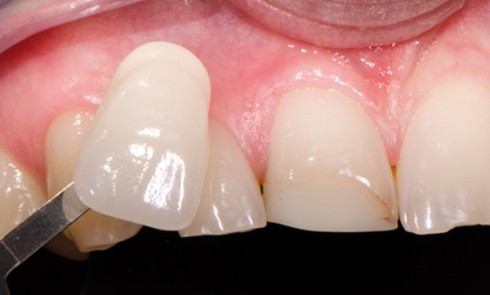

Article réservé à nos abonnés Réhabilitation d’une incisive centrale

1. Vue vestibulaire de l’ancienne restauration en composite. Une visualisation de la teinte de base est effectuée. 2. Après une prise...